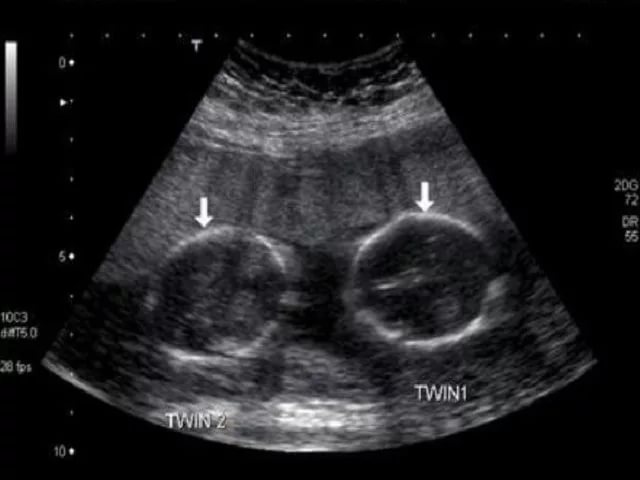

Подтвердили беременность 6 недель. 2 плодных яйца⚠⚠⚠Одно правильной формы с соответствующим сроку размером эмбриона, второе плодное яйцо деформированной фомы с отстающим размером по сроку эмбрионом. И у того и у другого есть желточный мешочек и сокращение сердечной мышцы. Девочки у кого такое было расскажите!!!!какие у аас были исходы таких беременностей? Говорите как есть не бойтечь меня напугать. Надеюсь что у вас все закончилось хорошо🙏